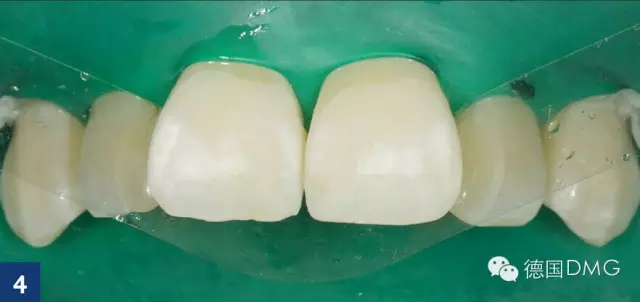

由于最初的酸蚀结果并不令人满意,因此我们重复酸蚀步骤. 利用乙醇干燥之后,可以看到颜色的改变。但是酸蚀结果还是不满意,因此我们进行了第三次酸蚀。在每一次酸蚀之后, 都应将酸蚀剂彻底冲洗干净然后用icon干燥剂进行干燥 (Fig. 4).

然后涂布icon渗透树脂并静置3分钟(Fig. 5), 将多余的材料清除后进行光固化 (Fig. 6). 重复此步骤,静置时间缩短为1分钟.